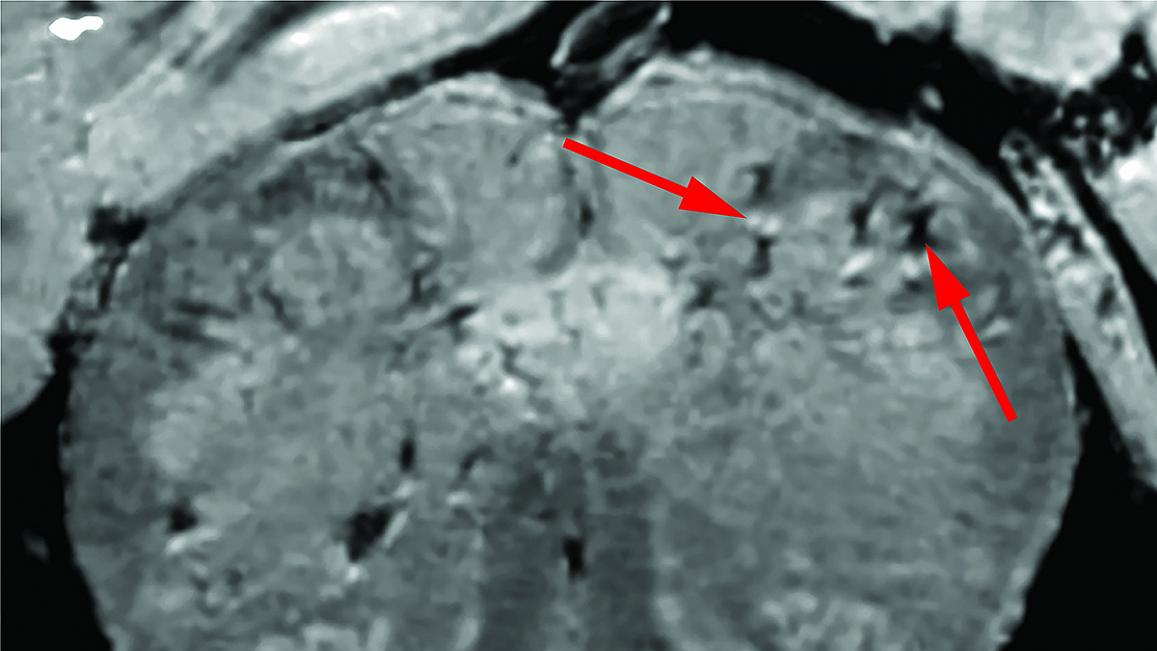

Initially, the researchers used a special, high-powered magnetic resonance imaging (MRI) scanner that is four to 10 times more sensitive than most MRI scanners, to examine samples of the olfactory bulbs and brainstems from each patient. These regions are thought to be highly susceptible to COVID-19. Olfactory bulbs control our sense of smell while the brainstem controls our breathing and heart rate. The scans revealed that both regions had an abundance of bright spots, called hyperintensities, that often indicate inflammation, and dark spots, called hypointensities, that represent bleeding.

The researchers then used the scans as a guide to examine the spots more closely under a microscope. They found that the bright spots contained blood vessels that were thinner than normal and sometimes leaking blood proteins, like fibrinogen, into the brain. This appeared to trigger an immune reaction. The spots were surrounded by T cells from the blood and the brain’s own immune cells called microglia. In contrast, the dark spots contained both clotted and leaky blood vessels but no immune response.